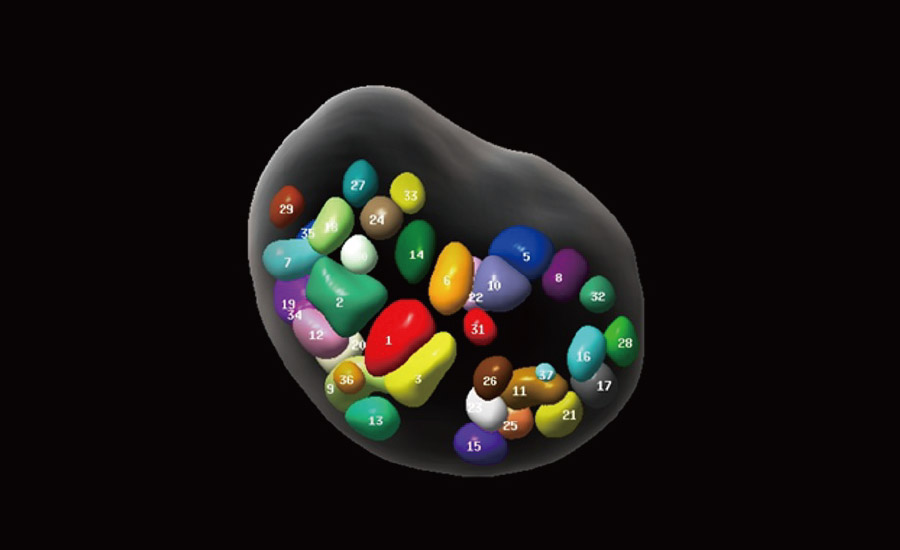

UMA (Ultra-Micro Angiography)

The innovative technology breaks the bottlenecks of traditional Doppler imaging. With ultra-high spatial resolution and flow sensitivity, it allows detecting super-subtle and super-slow flow perfusions, thereby extending the clinical application of qualitative and quantitative ultrasound evaluation in fetal brain, kidney, placenta, endometrium, ovary, etc.

3D UMA - perifollicular blood flow